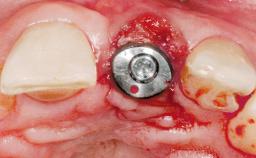

A 30-year-old female patient was referred to the office for the treatment of tooth 11. Her chief concern at the initial visit was to inquire, “Why is my tooth pink?” Upon clinical examination, it was determined that tooth 11 had a previous history of trauma and that the clinical crown had become noticeably pink in color as a result of internal resorption. This diagnosis was confirmed radiographically, indicating a large radiolucency involving the central and distal portions of the clinical crown. It was determined that restoration of this tooth was not possible, and that extraction was indicated. The presence of a mid-line diastema, which the patient wanted to reproduce, directed the treatment plan for tooth replacement utilizing a dental implant.

Type of Implants One-Piece|Reduced-Diameter

Bone Augmentation Horizontal|Simultaneous

Augmentation Materials Autogenous chips|Membrane

Placement Protocol Immediate implant placement

Socket Integrity Sufficient, with intact bone walls

Bone Volume Sufficient, with intact walls